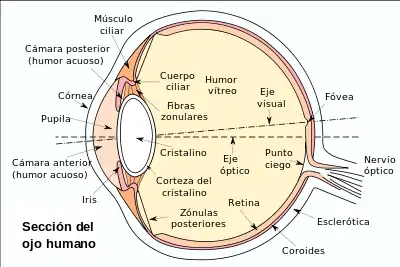

Dibujo esquemático del ojo humano. | ||

La estructura y el funcionamiento del ojo es muy similar en la mayoría de los vertebrados. El globo ocular es básicamente una esfera llena de un líquido transparente, llamado humor acuoso, que está compuesto por un 99 por ciento de agua. La pared está formada por 3 capas: la más interna o retina, la intermedia o coroides, y la más externa, que se llama esclerótica.

Posee una lente llamada cristalino, que es ajustable según la distancia; un diafragma, que se llama pupila (cuyo diámetro está regulado por el iris), y un tejido sensible a la luz, que es la retina.

Con la excepción de los peces, anfibios y ofidios, el enfoque se consigue gracias al cambio de forma del cristalino mediante un músculo llamado músculo ciliar.

La luz penetra a través de la pupila, atraviesa el cristalino y se proyecta sobre la retina, donde se transforma, gracias a unas células llamadas fotorreceptoras, en impulsos nerviosos, que son trasladados, a través del nervio óptico, hasta el cerebro.

Los ojos de todos los vertebrados comparten un modelo de circuito retiniano común: cinco clases de neuronas, dispuestas en tres capas nucleares que flanquean dos capas sinápticas.[10]

Los músculos extrínsecos del globo ocular son los mismos en todos los vertebrados, incluido el hombre.[11]